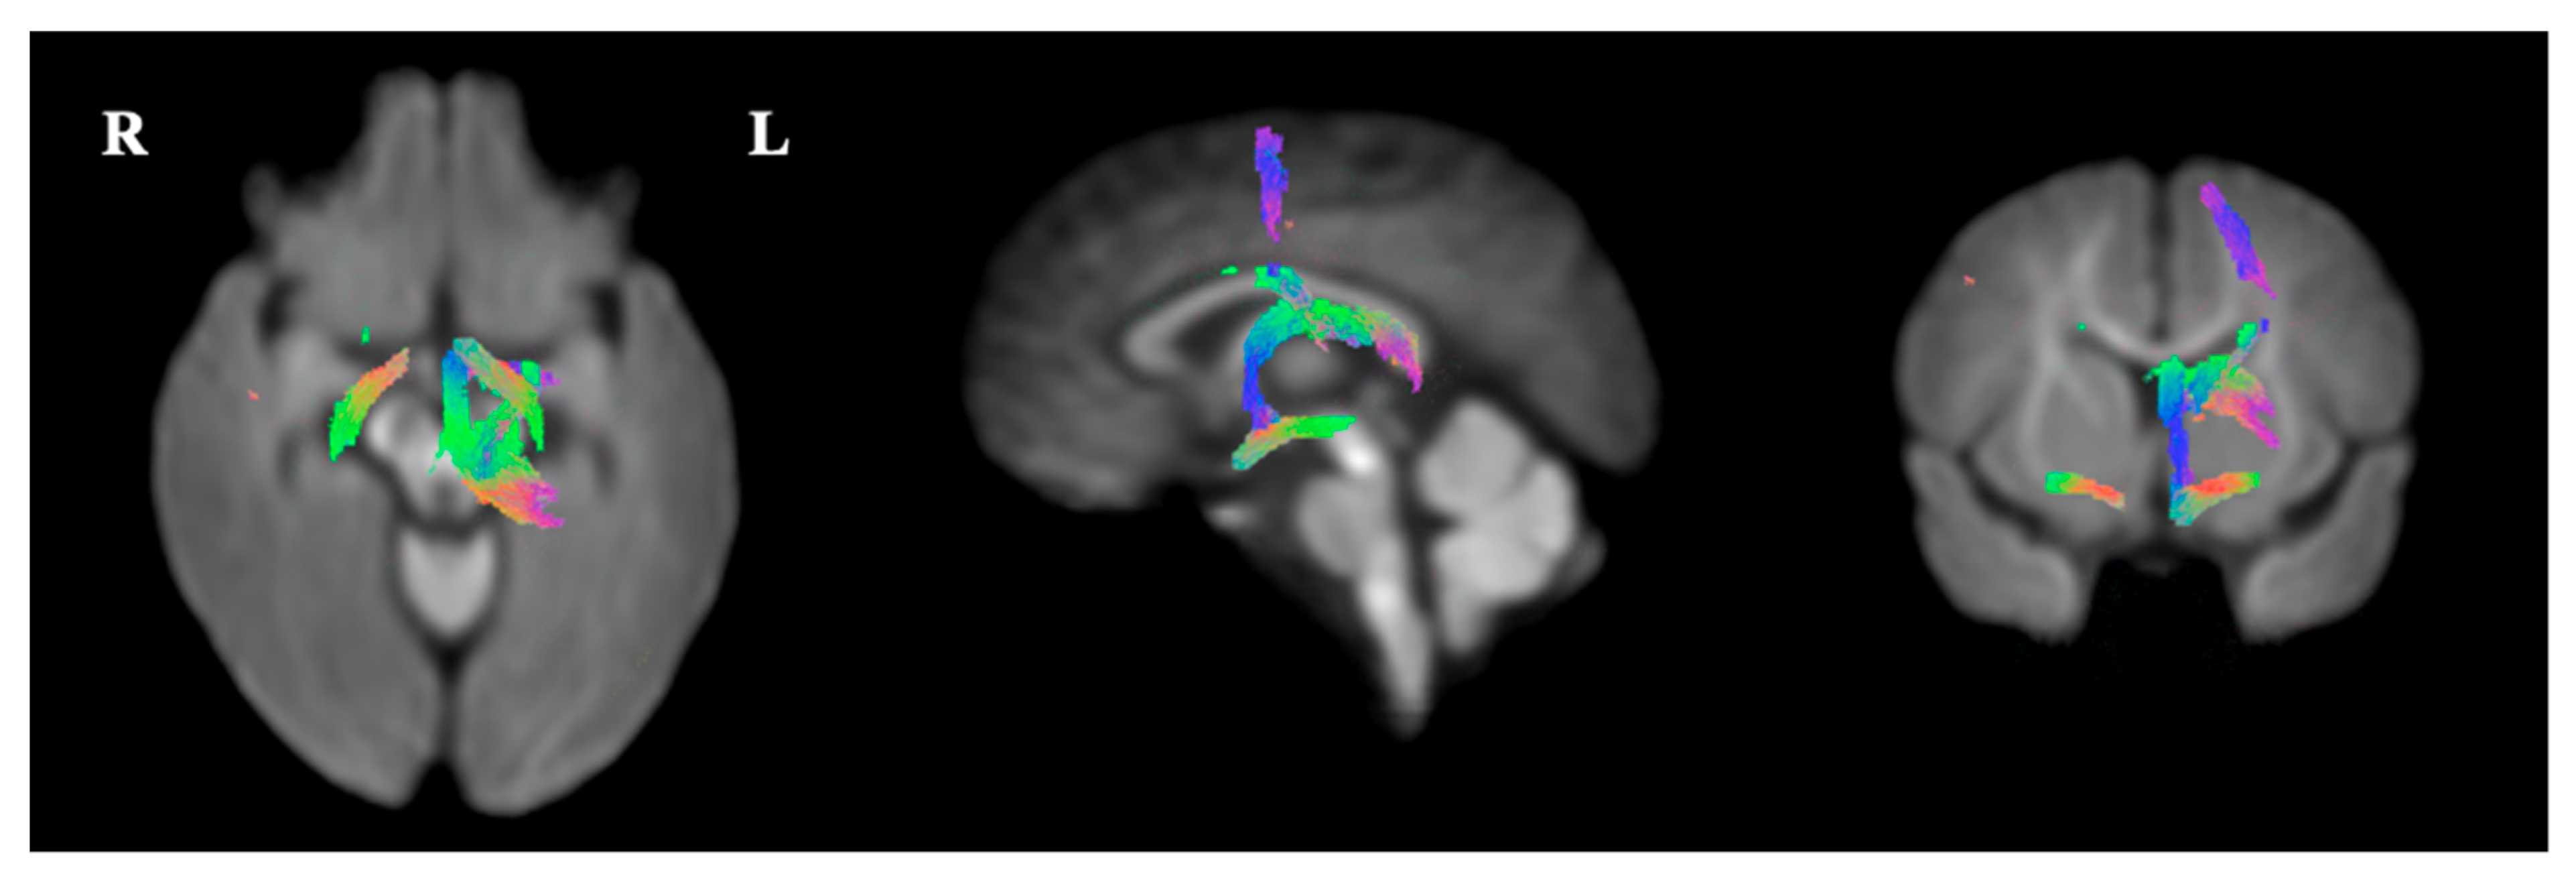

3.4. Fixel-Based Diffusion